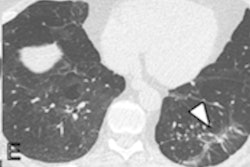

Like many acute lung injuries, the most common imaging finding for EVALI is ground-glass opacities with varying degrees of consolidation and tending to be predominant in the lower lobes of the lungs, Kligerman noted. He also listed these common findings -- data which came from the Chest study:

Parenchymal lung sparing can manifest in a few different patterns, with subpleural sparing most common (78%), followed by lobular sparing (59%), Kligerman said. He and his colleagues also found peribronchovascular sparing in 40% of EVALI patients. Almost a quarter (23%) of patients had all three sparing patterns.

So how can clinicians differentiate EVALI from COVID-19? It's tricky because both will manifest signs of organizing pneumonia. But there are some key differences. Sometimes EVALI patients present with gastrointestinal symptoms such as nausea and vomiting, diarrhea, and abdominal pain, which don't tend to be symptoms of COVID-19 and may help distinguish the two conditions, he noted. Imaging findings uncommon with COVID-19 include the following:

- Peribronchovascular sparing